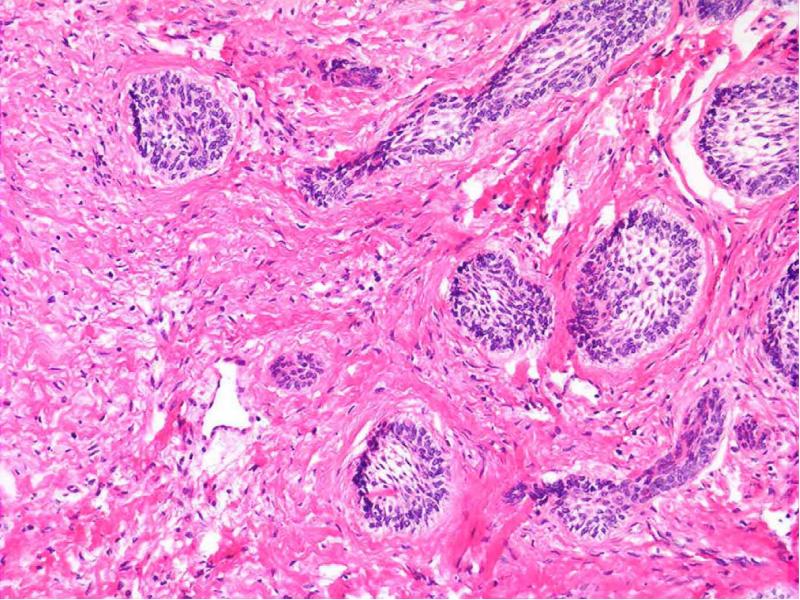

- 14. Микроскопическая картина Гистологически напоминает эмалевый орган Кистозная Фолликулярная Плексиформная Акантоматозная Базально-клеточная